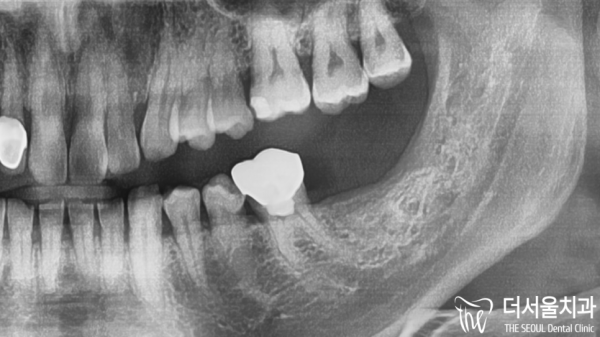

디지털치과인 태평역 더서울치과에서는 디지털임플란트인

네비게이션 임플란트 방식으로 임플란트 식립계획을 세우고

실제 임플란트 역시 모의수술을 한 그대로 심어드리고 있습니다.

보이시는 것 처럼 컴퓨터를 통해 조직과의 거리, 위치를 눈으로

확인하고 심을 수 있기 때문에 안전하고 정확하게 심을 수 있습니다.

The Seoul Dental Clinic in Taepyeong Station, a digital dental clinic, has digital implants

Plan for implantation using the navigation implant method

The actual implant is also being planted as it is.

As you can see, you can see the distance and location of the organization through the computer

You can check and plant it, so you can plant it safely and accurately.

치료는 이렇게 마무리 되었습니다.

주요 조직들과 가까운 위치때문에 쉬운 과정은 아니었지만

태평역치과 더서울치과에서는 안전하고 정확하게 임플란트를

심을 수 있었답니다.

The treatment ended like this.

It wasn't an easy process because of its proximity to major organizations

Taepyeong Station Dental Clinic The Seoul Dental Clinic provides safe and accurate implants

I was able to plant it.